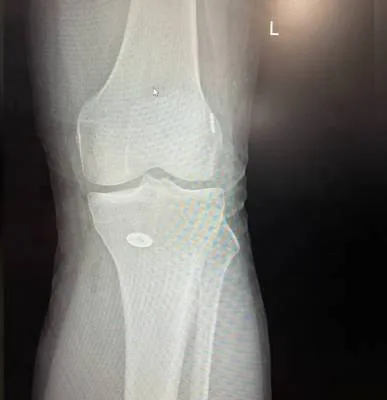

Dr. Haytham Elkhatib is a distinguished orthopaedic surgeon specializing in comprehensive musculoskeletal care. With expertise in trauma, fracture treatment, and advanced interventional joint injections, he offers innovative solutions for various conditions.

I had surgery with Dr. Haytham, and I’m very happy with the results. He previously operated on my leg after a fracture, and that surgery was very successful. Recently, I had another surgery on my knee, which was done in the simplest and most professional way. After the operation, I was able to return to my normal life — I can play football and be active again after a long time of not being able to. Dr. Haytham and his team took great care of me throughout the process, and I truly thank him for his excellent work and dedication